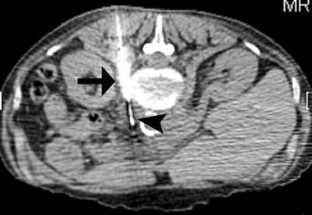

Fig. 3